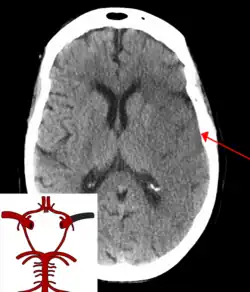

![]() | |

| CT scan of the brain showing a massive, prior right-sided ischemic stroke from blockage of an artery. Changes on a CT may not be visible early on.[1] | |

The most significant risk factor for stroke is high blood pressure.[7] Other risk factors include high blood cholesterol, tobacco smoking, obesity, diabetes mellitus, a previous TIA, end-stage kidney disease, and atrial fibrillation.[2][7][8] Ischemic stroke is typically caused by blockage of a blood vessel, though there are also less common causes.[13][14][15] Hemorrhagic stroke is caused by either bleeding directly into the brain or into the space between the brain's membranes.[13][16] Bleeding may occur due to a ruptured brain aneurysm.[13] Diagnosis is typically based on a physical exam and supported by medical imaging such as a CT scan or MRI scan.[9] A CT scan can rule out bleeding, but may not necessarily rule out ischemia, which early on typically does not show up on a CT scan.[10] Other tests such as an electrocardiogram (ECG) and blood tests are done to determine risk factors and possible causes.[9] Low blood sugar may cause similar symptoms.[9]